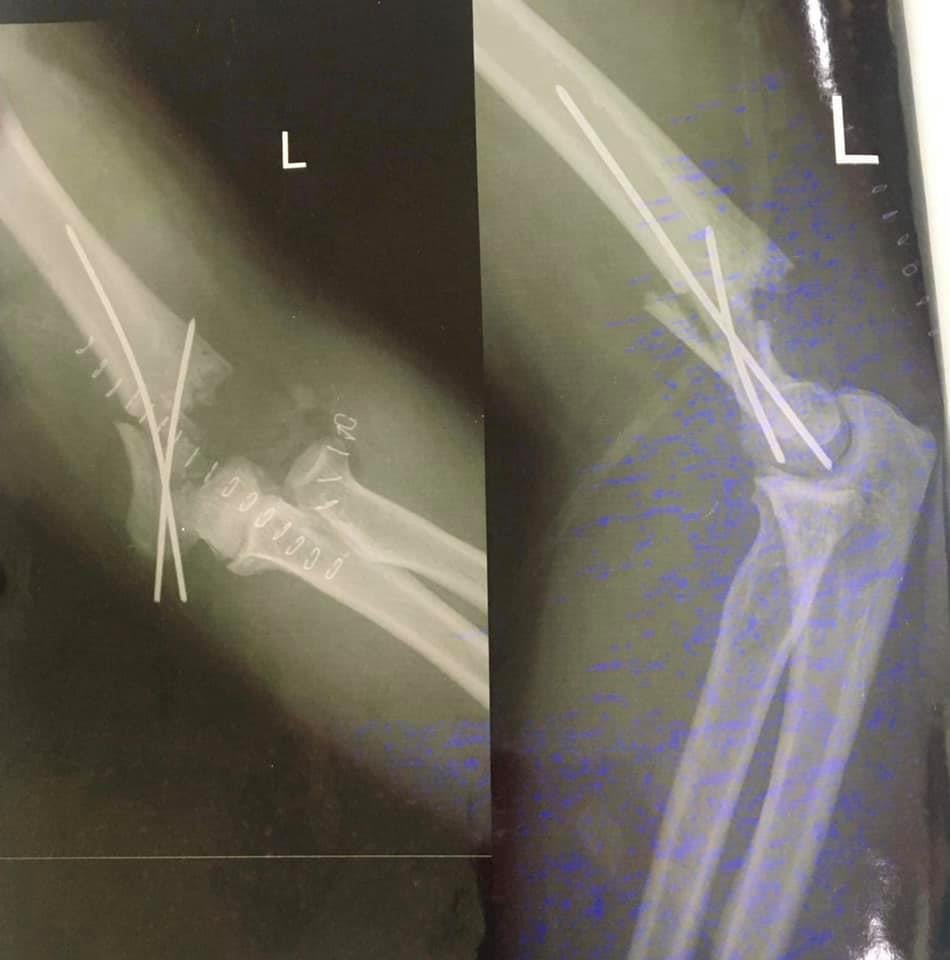

Гэмтэл Согог Судлалын Үндэсний Төвийн зөвлөх эмч, Монгол Улсын Хүний Гавьяат эмч Б.Бүргэдээр ахлуулсан Гар сарвуу нөхөн сэргээх бичил мэс заслын тасгийн баг хамт олон Монголд анх удаа “ТОХОЙНЫ ҮЕ БҮТЭН СОЛИХ” мэс заслыг амжилттай хийлээ.

Гавьяат эмч Б.БҮРГЭД: Монголд анх удаа 20-н жилийн өмнө багштайгаа хамт мөрний үе солих мэс засал хийж нутагшуулж байлаа. Тус мэс засал нь өнөөдөр өдөр тутамд хийгддэг болсон. Тохойн үений бэртэл гэмтэл ихэссэн учир багийн нөхөдтэйгөө хамтарч Монголдоо анх удаа энэ төрлийн мэс заслыг маш амжилттай хийлээ. Цаашдаа энэ мэс заслыг нутагшуулах бололцоотой. Энэ мэс заслыг хийснээр Хөдөлмөрийн чадвар алдалтыг бүрэн зогсоож, тухайн хүний амьдралын чанар сайжрах боломжтой юм.